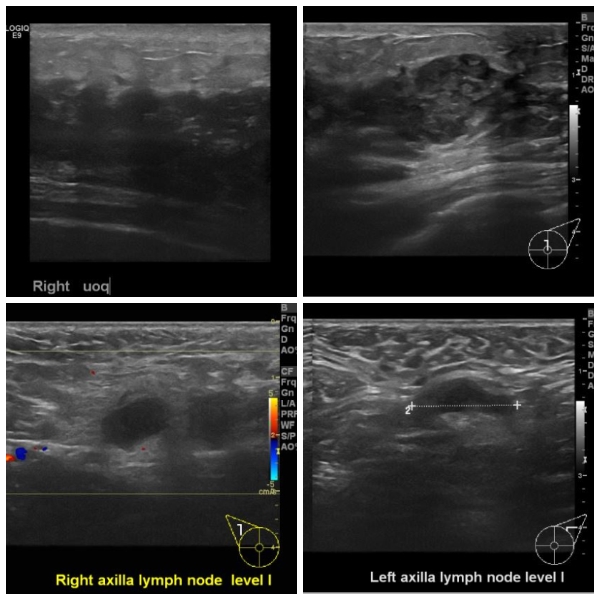

양측 유방에 만저지는 몽우리로 내원하신 30대 여성분으로  양측 유방의 혹과, 겨드랑이에 만저지는 몽우리 조직검사와 세포검사 시행하여 양측 침윤성 유관암과, 양측 겨드랑이

전이로 진단 되었습니다.